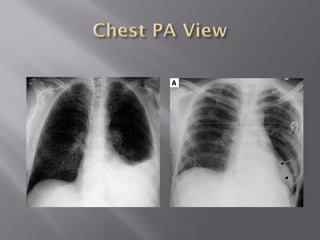

 The patientshould be positioned sitting upright for 10-20 minutes prior to acquiring the erect chest X-ray image.  This allows any free intra-abdominal gas to rise up, forming a crescent beneath the diaphragm. It is said that as little as 1ml of gas can be detected in this way.

 Rupture ofa hollow viscus  Perforated peptic ulcer  Trauma  Perforated diverticulitis (usually seals off)  Perforated carcinoma  Post-op --5-7 days normal, should get less with successive studies  NOT ruptured appendix (seals off)

Free air underthe diaphragm Best demonstrated on upright chest x rays or left lat decubitus Easier to see under right diaphragm